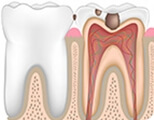

These issues cause tooth painRoot canal needed

Deep Cavity

Pulp Necrosis

Pulp Inflammation

Broken Crown & Root

Periapical Periodontitis

Explore how pulpitis and periapical periodontitis develop

Root canal is the best treatment for pulpitis and periapical periodontitis